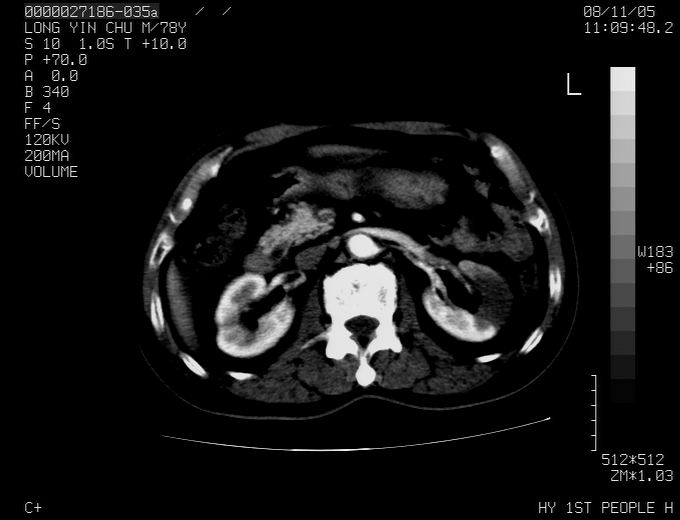

标题: CT16532:M78Y,肝脏病变,请会诊 [打印本页]

标题: CT16532:M78Y,肝脏病变,请会诊

腹胀,腹痛就诊,男性,78岁,外院b超未见异常。

支持脾肾转移瘤,双侧胸腔积液。

考虑弥漫性肝癌并脾及双肾转移.双侧胸水.

肝脾肾转移瘤可能性大,左肾不除外梗塞,双侧胸水

考虑肝癌并双肾及脾脏转移;双侧胸腔积液。